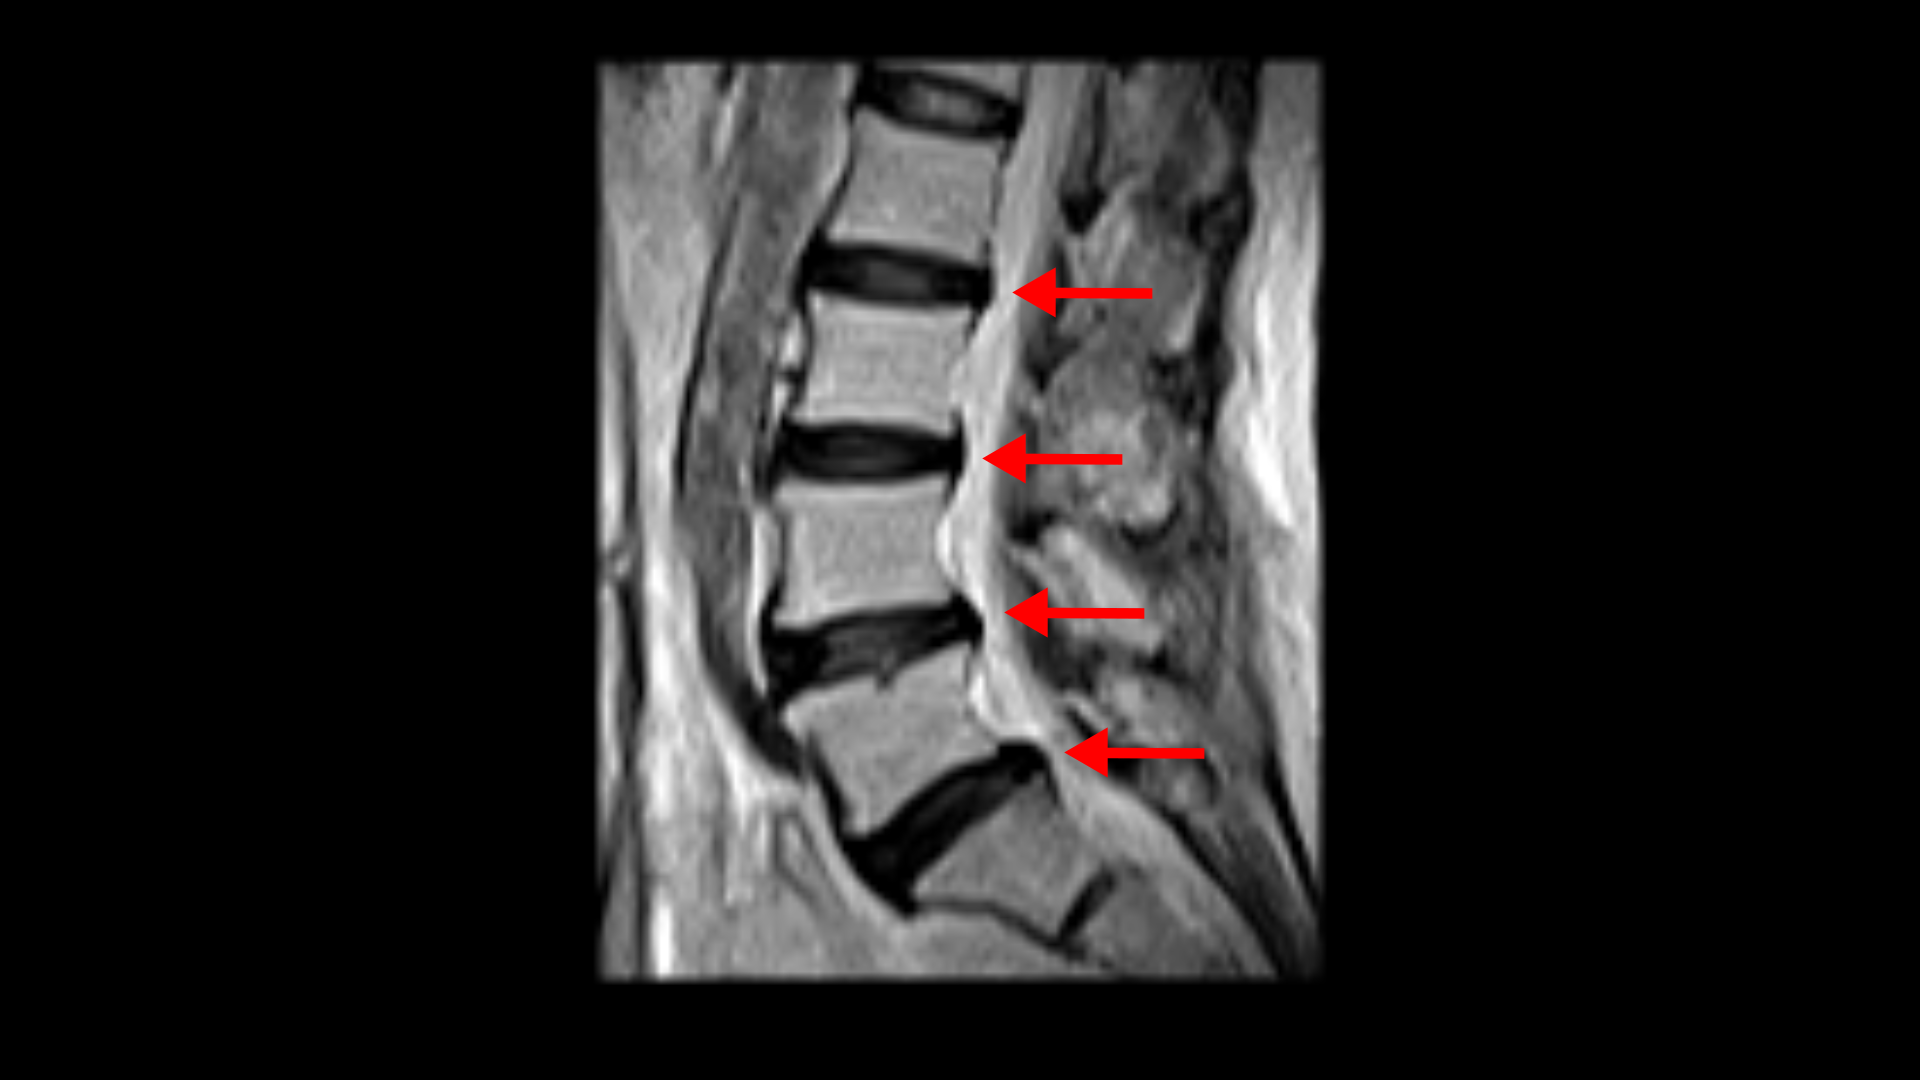

우선 이 환자분의 X-ray를 보면 5번 1번에 전방전위증으로 인한 불안정성이 있습니다. 척추가 불안정하므로 전방전위로 뼈가 밀려 나간 정도가 MRI에 보이는 것보다 X-ray 굴곡상태에서 보는 게 훨씬 더 심해 보입니다. 또 척추 여러 마디에 퇴행성 병변이 보입니다.

먼저 5번 1번에 척추관 내의 황색인대의 골화 현상이 보이고

후관절의 퇴행도 심해 보입니다.

또 흉추 두 마디에서도 역시 황색인대의 골화 현상이 보입니다.

그리고 허리 4마디에 퇴행성 허리디스크가 있습니다.